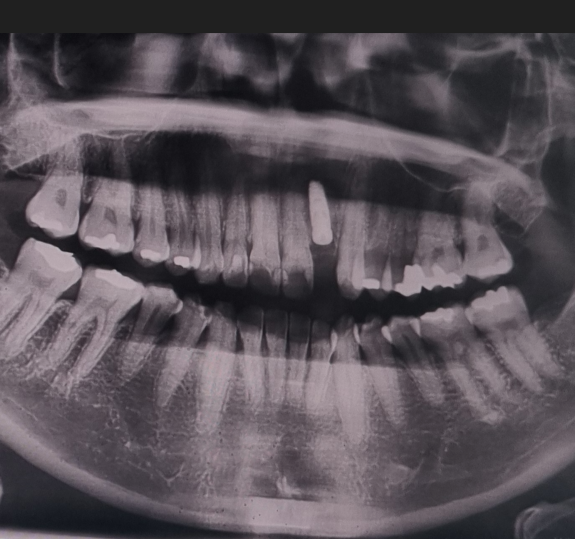

저의 경험상 항암치료를 하면 피부, 항문, 관절통 뿐만 아니라 치아에도 엄청 영향을 주는 것 같아요. 독한 항암제 성분이 우리 입 속 침에도 남아있어서 그런 것 같습니다. 하지만 항암치료를 하면 감염이나 지혈 등에 문제가 발생할 수 있기 때문에 치과치료는 간단한 스케일링도 하지 말라는 안내를 받습니다. 그래서 보통 항암 시작 전에 시간적인 여유가 있다면 치과진료를 미리 받으라고 안내를 받는데, 저는 암수술과 항암치료 시작이 너무 촉박하게 진행되어서 아무런 준비를 못하고 항암을 시작하게 되었습니다. 저는 아이스항암을 6차 진행했는데, 4차까지는 구내염과 잇몸통증으로 고생을 했었고 5차부터 치아 시림 등 통증이 발생해서 막판에 고생을 많이 한 케이스입니다. 그때까지는 주치의 선생님이 치과치료를 하면 안 된다고 하셨었고, 이가 많이 아픈 것은 아니라서 계속 참아왔고 10월에 항암치료 종료 및 1월 추적검사 1차때 피검사 결과 등을 바탕으로 주치의선생님께 치과치료 허락을 받았습니다.

1차 방문 (진단 및 치료계획 설명)

- 사진을 찍어 정확한 치아 상태 파악합니다.

- 사진을 보면서 진료를 진행할 의사에게 설명을 듣습니다.

2차 방문 (수술)

- 체감상 1시간 넘게 진행한 것 같은데, 수술 후 결과 사진 찍고 설명 듣고 나오니 12시 40분;;